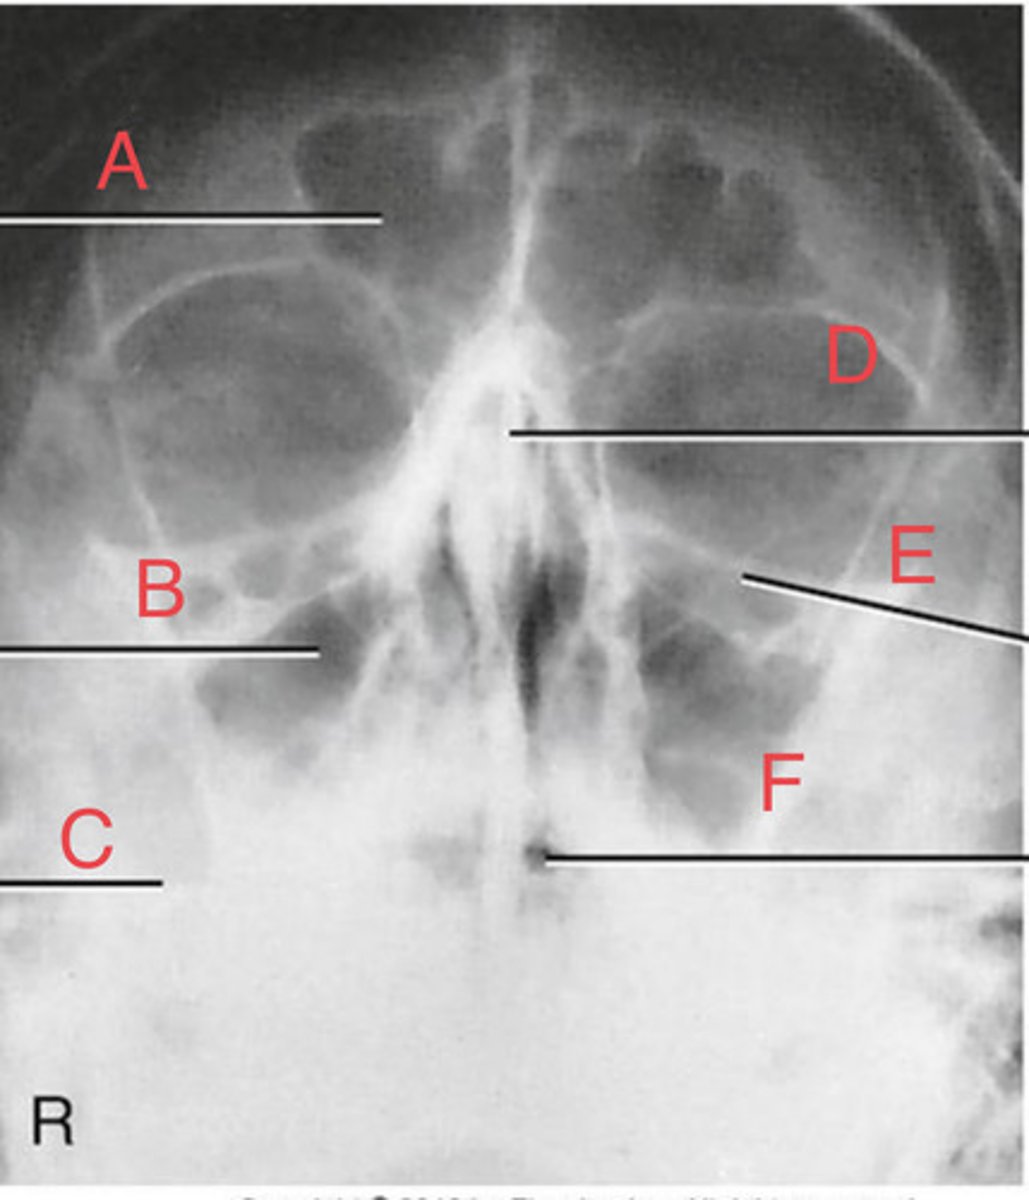

Waters sinus method

What projection?

r. frontal sinus of the frontal bone

A.

R. Maxillary sinus of maxilla

B.

R. petrous ridge of temporal bone

C.

bony nasal septum

D.

L. inferior orbital fissure of sphenoid bone

E.

Sphenoid sinus of sphenoid bone

F.

bony nasal septum

E.